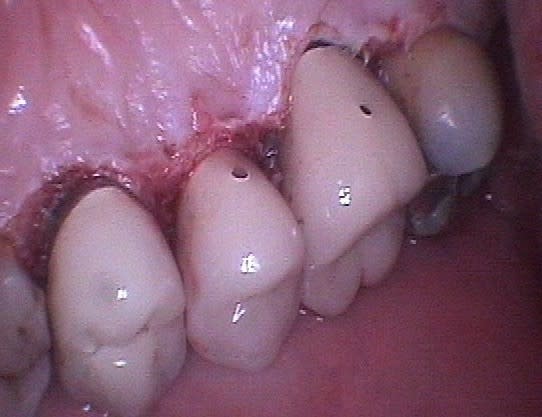

Marc, évidemment qu'il s'agit de gingivectomie, je dirais même plutôt gingivoplastie, la gencive est sculptée par le laser plus fidèlement qu'avec un bistouri ou une fraise car il suit exactement le trajet et la profondeur de chaque poche sans sectionner à l'emporte pièce.

J'ai rajouté les photos vestibulaires sur mon premier post, les poches étant un peu moins profondes qu'en palatin.

La différence ne s’arrête pas seulement là, car comme te l'a très bien expliqué Emma, le laser représente bien plus qu'un simple instrument de coupe ou de nettoyage, aucun bistouri ni aucune curette n'est capable de stériliser, d'assurer l'hémostase immédiate, d'activer la cicatrisation ou encore de pratiquer une suture avec un confort pour le patient nettement amélioré. Tu pourrais à la rigueur le comparer à un bistouri électrique mais celui-ci n'a qu'un effet de surface limité.

Un exemple: une 46 avec furcation linguale dénudée après lasérisation et restauration par une endocouronne céromère réalisée il y a 9 ans et sans signe clinique avec une excellente attache gingivale malgré la perte osseuse, les 3 avant dernières images ont été prises lors d'un contrôle en mars dernier ...

9 années pour cette patiente de 90 ans, cela vaut bien le coup d'essayer vous ne croyez-pas? (dernière radio)

Avec le laser, on devient bien plus conservateur...